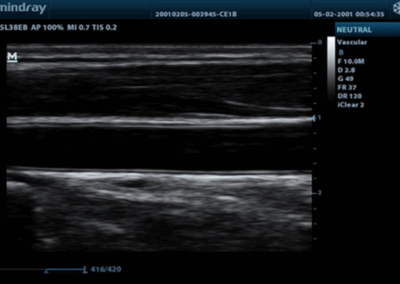

DP-20

Sistema de ultrasonido.

La opción ideal para un sistema de ultrasonido blanco y negro básico, ofrece una combinación excepcional de rendimiento y precio asequible. Con una nueva plataforma basada en el potente procesador Intel, el DP-20 forma parte integral de la nueva generación de sistemas de ultrasonido blanco y negro portátiles de Mindray, equipados con las últimas tecnologías de imagen y prácticas opciones de flujo de trabajo.